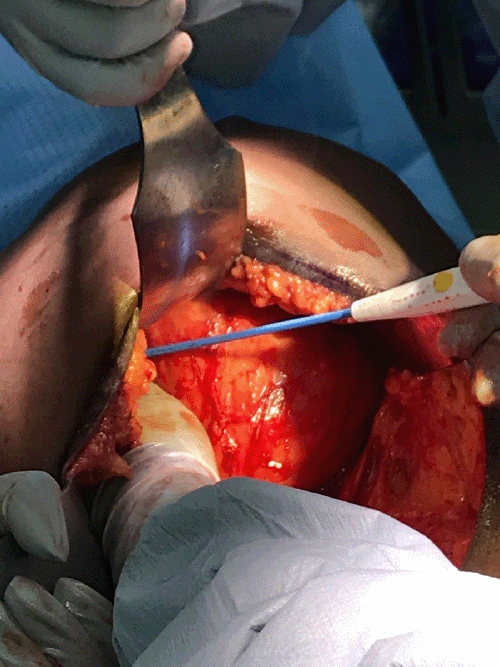

Figure 3. Intraoperative Dissection of Right Breast Mass. Published with Permission

The breast skin was everted, and the primary surgeon delivered the mass through the incision with the help of two assistants (Figure 3). The mass was dissected free, passed to the back table to be weighed, and sent to surgical pathology for permanent section.